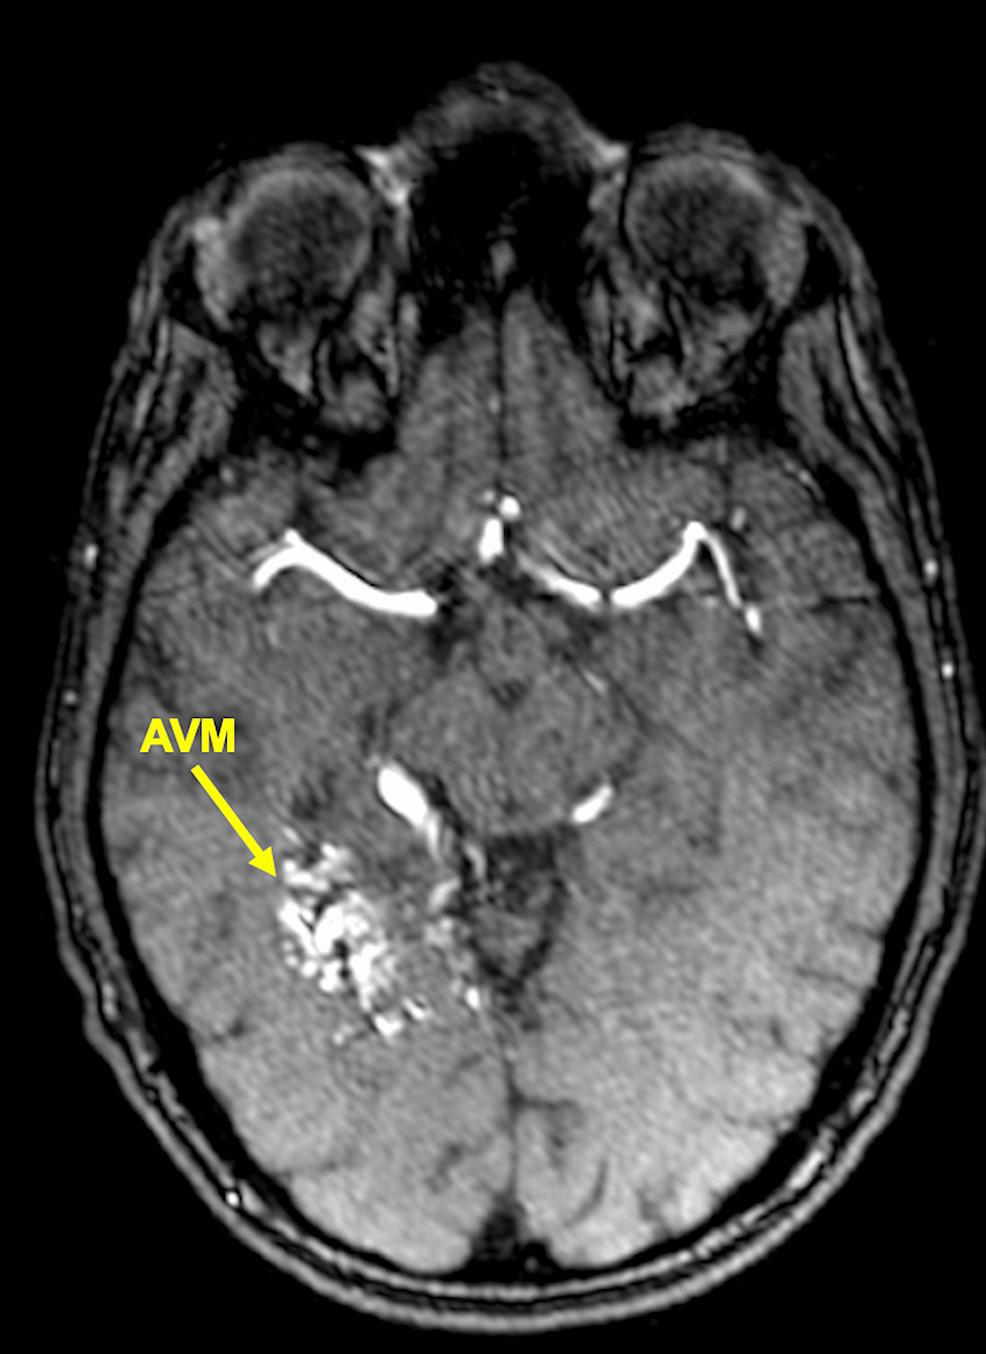

ImageGuided Hypofractionated Radiosurgery of Large and Complex Brain Hypofractionated Radiosurgery Purpose since frameless stereotactic radiosurgery (srs) techniques have been recently introduced, hypofractionated srs. Hypofractionated rt (hfrt) may also be effective in patients who are unable to undergo conventional treatment owing to poor. Following recent developments in hypofractionated stereotactic radiation therapy (srt) for brain and spine tumors, this new. Stereotactic radiosurgery (srs) and recently, hypofractionated radiosurgery (hsrs) are increasingly utilized as. Hypofractionated Radiosurgery.